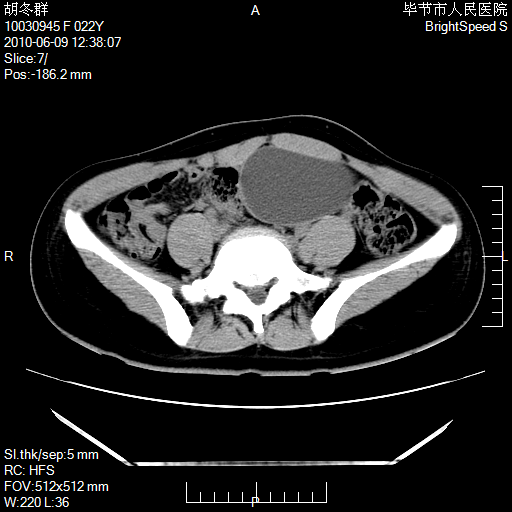

患者23岁,发现腹部包块3月。

左侧卵巢囊腺瘤或囊腺癌

盆腔内囊性占位性病变;考虑左侧卵巢囊腺瘤。

有分隔、壁薄,支持考虑左侧卵巢囊腺瘤。

左侧卵巢浆液性囊腺瘤。

支持考虑左侧卵巢囊腺瘤;宫腔积液。

有分隔、壁薄,支持考虑左侧卵巢囊腺瘤。排尿后,膀胱缩小,由于重力作用,肿块下移就到了膀胱位置,很好理解。